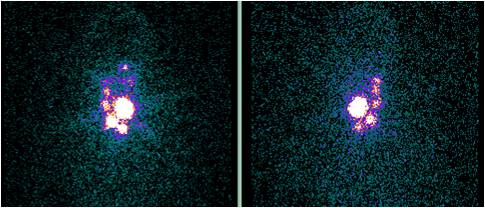

甲状腺癌颈部淋巴结转移第1次131碘治疗后显像

甲状腺癌颈部淋巴结转移第2次131碘治疗后显像(转移淋巴结完全清除)